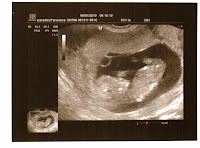

And sure enough it was! That damn little thing!! With the new battery I found the heartbeat straight away (ok....with a bit if fiddling!) and according to our counting it was at around 160bpm! How lovely! I of course checked mine too, just to make sure it wasn't me having a heart attack... nope, definitely not mine! I have to make sure I am not getting addicted...I'll try to use it no more than twice a week (even because if it uses up batteries at the speed of light we'll spend twice as much money in a matter of days!).